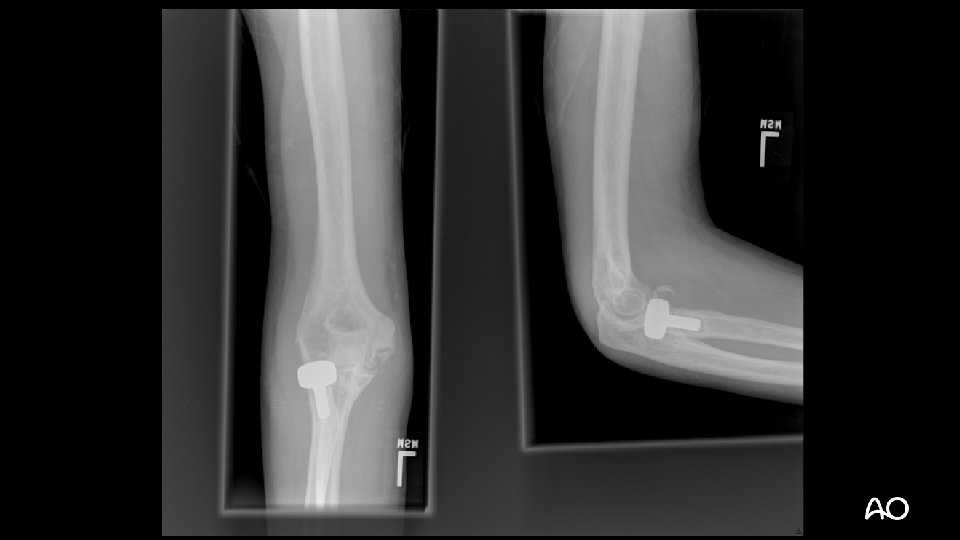

Case 1

Terrible triad fracture dislocation • Historically poor outcomes • Injury “triad”: • Elbow dislocation (often posterior) • Radial head fracture • Coronoid fracture

Terrible triad • Treatment principles: • Repair coronoid/anterior capsular attachment • Repair or replace radial head • Repair LCL • NEVER CREATE MORE INSTABILITY: • Ignore “small” (fleck) coronoid fractures: • These are NOT “avulsion” fractures by brachialis, as radiologists often like to say on their x-ray reads • Resect radial head without replacing it • MCL does not usually need operative repair